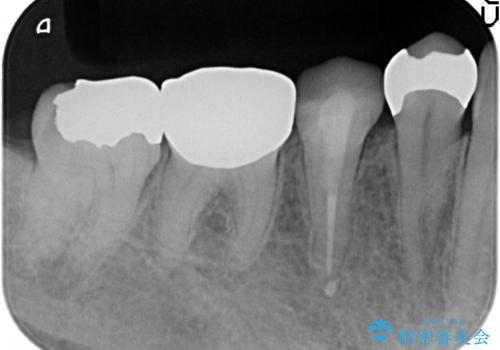

診査の結果右下6の歯の神経が死んでいたため、根管治療を行いました。

その後症状の消失を確認し、オールセラミッククラウンによる補綴を行いました。